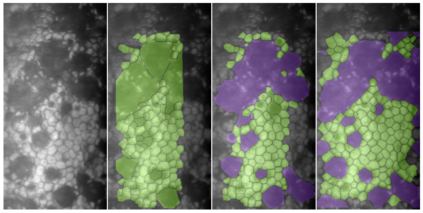

Specular microscopy assessment of the human corneal endothelium (CE) in Fuchs' dystrophy is challenging due to the presence of dark image regions called guttae. This paper proposes a UNet-based segmentation approach that requires minimal post-processing and achieves reliable CE morphometric assessment and guttae identification across all degrees of Fuchs' dystrophy. We cast the segmentation problem as a regression task of the cell and gutta signed distance maps instead of a pixel-level classification task as typically done with UNets. Compared to the conventional UNet classification approach, the distance-map regression approach converges faster in clinically relevant parameters. It also produces morphometric parameters that agree with the manually-segmented ground-truth data, namely the average cell density difference of -41.9 cells/mm2 (95% confidence interval (CI) [-306.2, 222.5]) and the average difference of mean cell area of 14.8 um2 (95% CI [-41.9, 71.5]). These results suggest a promising alternative for CE assessment.